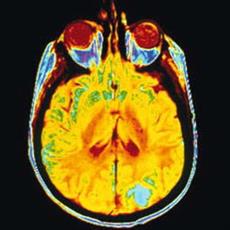

تومور مغزی عبارت است از رشد یک توده غیرطبیعی در مغز که امکان دارد خوش خیم یا بدخیم باشد.

نوعی ضایعه فضاگیر داخل جمجمه ای است.